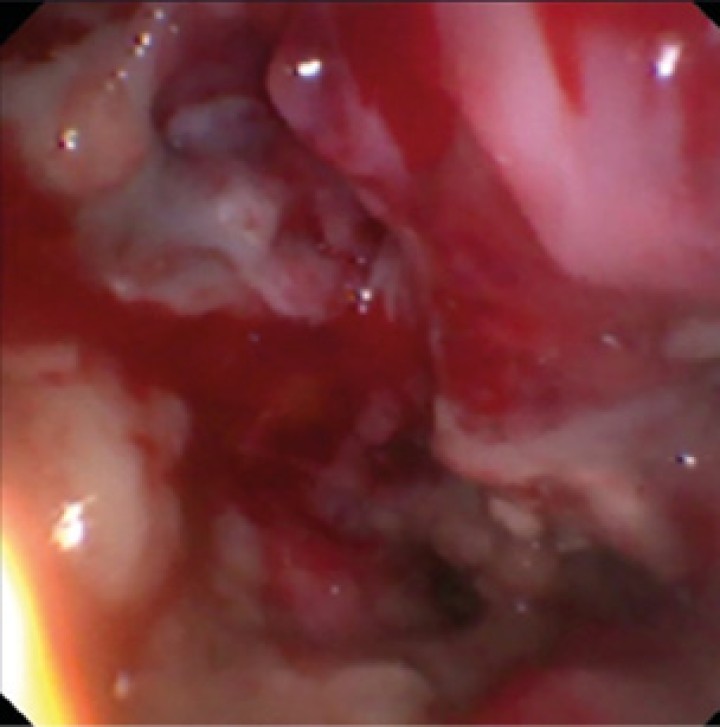

Como terapia se optó por la aplicación tópica intranasal de una pomada depot de clotrimazol 1 % (Ginecanesgen pomada 20 mg/g, Bayer, Barcelona) dada su alta efectividad y la necesidad de menos tiempo anestésico.[ Billen F, Peeters D: Canine aspergillosis. En Ettinger SJ, Feldman EC, Cote E (8th): Textbook of Veterinary Internal Medicine. Misouri, Saunders Elsevier, 2017: 1035-1039. , Sharman MJ, Mansfield CS. Sinonasal aspergilosis in dogs: a review. Small Anim Pract 2012; 53(8): 434-44. [PubMed] , Peeters D, Clercx C. Update on canine sinonasal aspergillosis. Vet Clin Small Anim 2007; 37: 901-916. [PubMed] , Ballber C, Hill TL, Bommer NX. Minimally invasive treatment of sinonasal aspergillosis in dogs. J Vet Intern Med 2018; 32(6): 2069-2073. [PubMed] , Hazuchova K, Neiger R, Stengel C. Topical treatment of mycotic rhinitis-rhinosinusitis in dogs with meticulous debridement and 1% clotrimazole cream: 64 cases (2007-2014). J Am Vet Med Assoc 2017; 250(3): 309-315. [PubMed] , Belda B, Petrovitch N, Mathews KG. Sinonasal aspergillosis: Outcome after topical treatment in dogs with cribriform plate lysis. J Vet Intern Med 2018; 32(4): 1353-1358. [PubMed] ] Previamente, se desbridaron las placas y se extrajeron mediante el uso de pinzas y sonda de aspiración junto con la aplicación de lavados con suero salino fisiológico (Vídeo 1, Fig. 3). A continuación, con el paciente en recumbencia esternal, se colocaron gasas en la nasofaringe y se aplicó la pomada a través de sondas urinarias (Kruuse, Langeskov, Dinamarca) (Vídeo 2) hasta ocupar toda la cavidad nasal izquierda con tejido afectado (aproximadamente 20 g), dejándola actuar 15 minutos. Posteriormente, se colocó la cabeza en posición declive inclinada hacia abajo para evitar la filtración de la crema hacia la faringe.

Aspecto tras el desbridamiento de la cavidad nasal izquierda (meato nasal), con ausencia del laberinto etmoidal. La mucosa presenta un aspecto eritematoso con focos de sangrado tras el proceso.